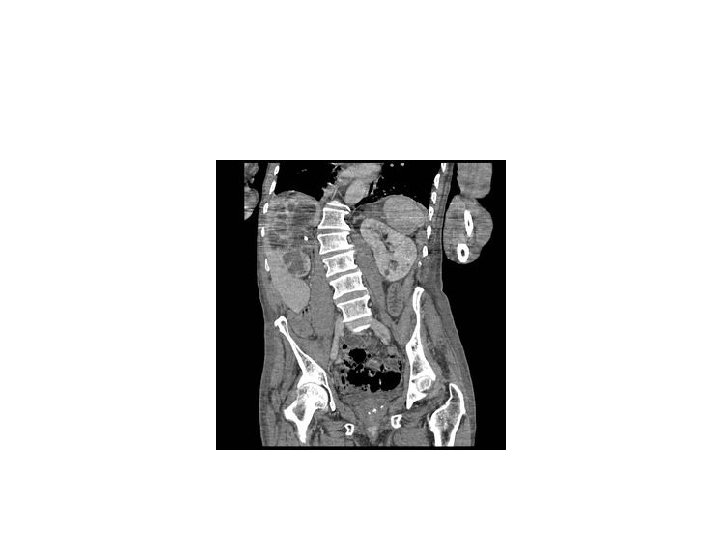

CT scan demonstrates a large heterogeneous left kidney, with dilated calyces and areas filled with lipid-laden macrophages. Xanthogranulomatouspyelonephritis is often associatedwith the presence of renalstones.

- Kidney becomes grossly enlarged, difficult to distinguish from RCC radiologically ( most cases Dx for presumed RCC)